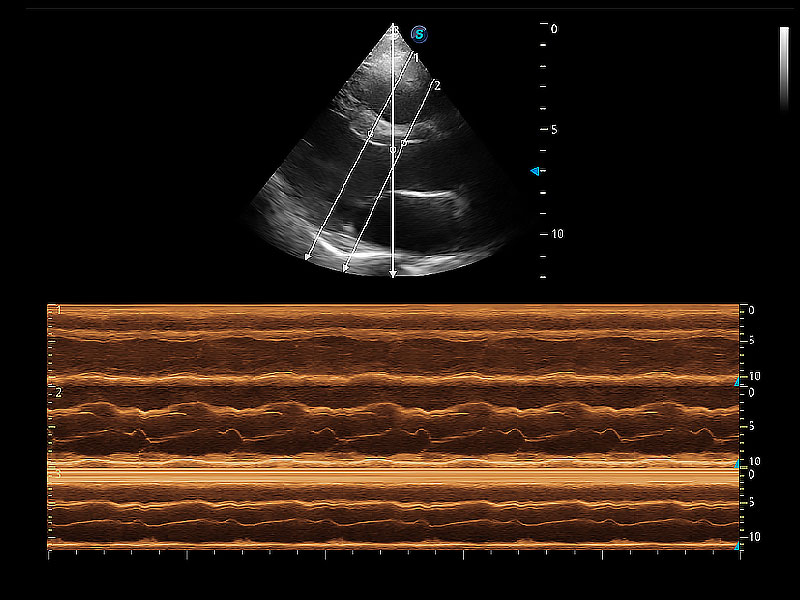

通過360度任意調(diào)節(jié)3條M型取樣線,在同一心動(dòng)周期上觀察心臟不同位置的運(yùn)動(dòng)曲線,得到準(zhǔn)確的心功能測(cè)量數(shù)據(jù),有效評(píng)估心肌運(yùn)動(dòng)及左心室功能。